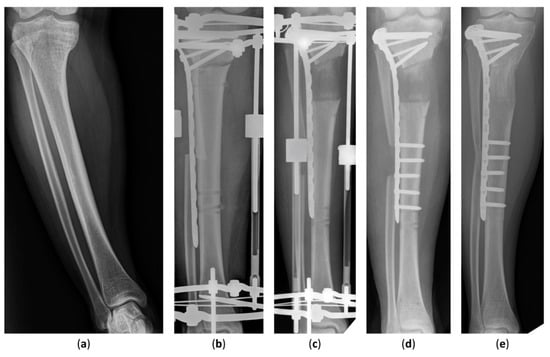

The latest postoperative radiographic measurements including the mLDFA, MPTA, and MAD are summarized in Table 3. The mean postoperative mLDFA was 85.0° (range, 79.5°–91.0°) in Group 1 and 86.5° (range, 80.0°–93.4°) in Group 2. The mean postoperative MPTA was 86.4° (range, 80.2°–93.5°) in Group 1 and 87.6° (range, 81.3°–93.5°) in Group 2. The postoperative MAD, the indicator of lower-limb malalignment, was 14.2 mm (range, 1.0–46.0 mm) in Group 1 and 6.7 mm (range, 3.0–13.0 mm) in Group 2. All in all, the postoperative mLDFA, MPTA, and MAD of Group 1 were not distinguishable from Group 2. The case of an 18-year-old girl with hypophosphatemic rickets who underwent acute angular correction and fixator-assisted lengthening is demonstrated in Figure 2 and Figure 3 at 40 months follow-up.

Figure 3. Lateral radiographs of an 18-year-old girl who underwent fixator-assisted plating and acute angular deformity correction for leg-length discrepancy. (a) A preoperative lateral view of the tibia. (b) The patient underwent tibial lengthening and deformity correction using an Ilizarov apparatus and a submuscular plate. (c) The distraction length and alignment were satisfied. (d) The distal part of the submuscular plate was fixed at removal of the external fixator. (e) Distraction osteogenesis was completed without complications 40 months after the procedure.